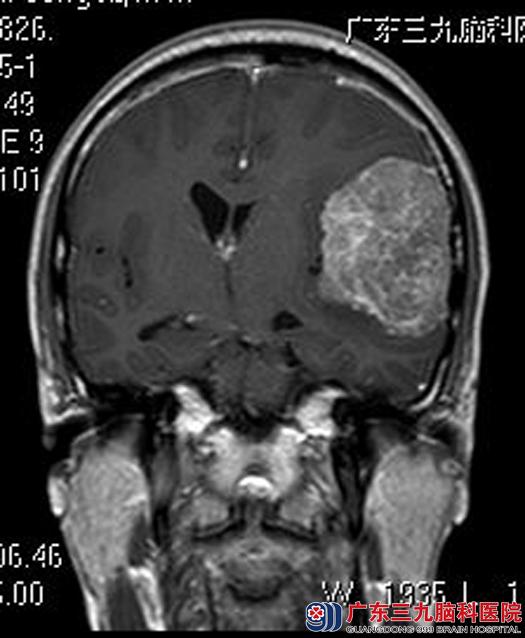

在亲属的陪同下,他们来到广东三九脑科医院。头颅MRI检查显示:左侧额颞部占位性病变,大小约6.9cm×3.9cm×6.2cm,考虑脑膜瘤。

由综合神经外科鲁明主任主刀,在全麻下行左侧额颞部脑膜瘤切除术,术中见肿瘤明显侵犯硬模,呈灰褐色,质中,血供丰富,在显微镜下将肿瘤全切。术后丘先生头痛症状明显好转,已康复出院。术后病理结果:过渡型脑膜瘤。